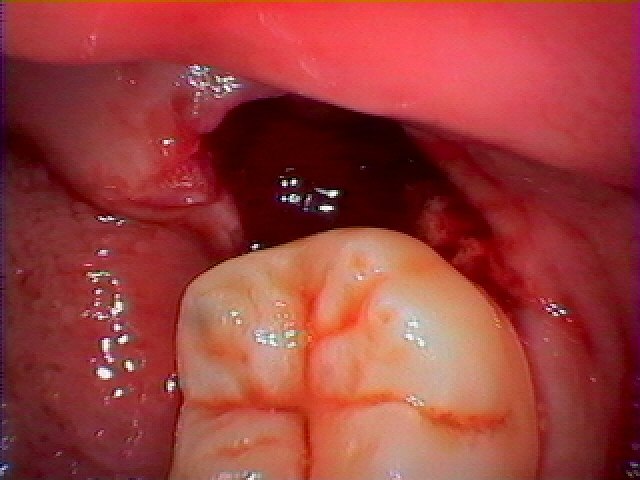

このように真横に向いている親知らずでした

歯冠部を分割して抜歯を行っていきました